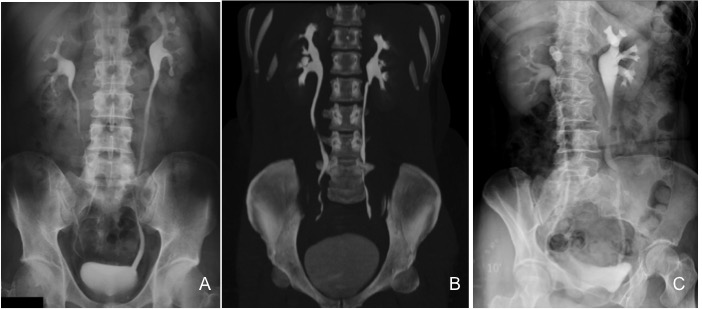

2- Urografía excretora:

No indicada sistemáticamente.

Delinea la anatomía de sistema pielocalicial y da una idea del epitelio del tracto urinario desde los riñones a la vejiga. Su debilidad radica en la dificultad para caracterizar masas (quistes, neoplasias, abscesos), falta de detalle parenquimatoso y la dependencia de la funcionalidad del riñón. Solo el 25% de pacientes con pielonefritis muestran signos de afectación en la urografía excretora.

B- Con el TCMD con contraste en fase excretora podemos estudiar las vías de manera más prescisa y hacer reconstrucciones. Estudio normal.

C- UIV de una hidroureteronefrosis izquierda leve (grado II/IV) hasta vejiga.